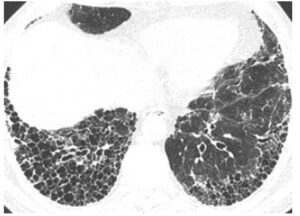

肺線維症は肺の高度の線維化が慢性かつ確実に進行する、非常に予後不良な不可逆性の間質性肺炎です。癌と変わりない予後だともいわれ、指定難病に位置付けられています(2)。この肺の高度線維化に伴う陰影はUIPパターンと呼ばれ、胸部CTで肺底部(横隔膜あたり)から背中にかけての蜂巣肺(ハチの巣状のボコボコした影)や網状影が特徴とされます。